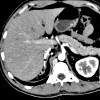

MRI of the spleen.

МРТ селезенки. Методика получения слоистых изображений органа путем сканирования области исследования радиочастотными импульсами в электромагнитном поле. Список инструментальных исследований селезенки очень ограничен (ультразвук, лиенография, сцинтиграфия), среди которых МРТ является наиболее точным и предпочтительным методом диагностики. МРТ позволяет оценить топографию, морфологическое строение селезенки, окружающих мягких тканей и сосудов, а также наличие в них патологических процессов. МРТ селезенки является чрезвычайно информативным инструментом для диагностики пороков развития органов, травматических повреждений, спленомегалии, нарушений кровообращения, онкологических процессов Осмотр проводится самостоятельно или как часть МРТ брюшной полости и может потребовать введения контрастного МРТ.